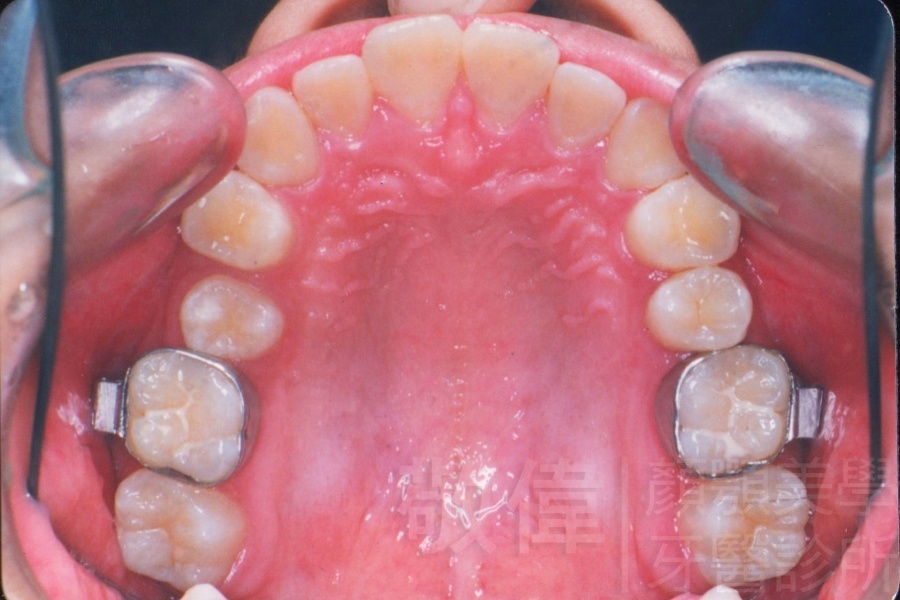

變臉矯正,原來戽斗妹跟大歪臉變成自信正妹

經由本院3D數影X光影像儀分析、與3D齒顎顏矯正技術,再配合口腔顎面正顎專科醫師施以正顎手術治療,雙方共同合作,使患者臉部外觀有很好的改善,大歪變小歪,產生了天南地北的大改變,她的人生也整個變得不一樣。

因為矯正與正顎手術的配合,使「戽斗妹」變成了「陽光正妹」,完全的改變了她的人生,在面對各種場合、與人交際都散發出自信微笑。所以,奉勸家長,如果小朋友有臉顎畸型的問題,應該考慮配合做這種簡單、安全、有效的正顎手術。